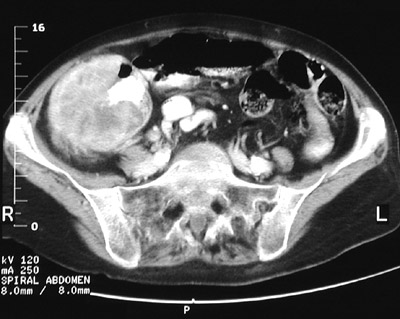

The large mass lesion seen in this abdominal CT scan with contrast is a large adenocarcinoma arising in the cecum. Cecal carcinomas often become bulky masses and may first be manifested by iron deficiency anemia from blood loss.